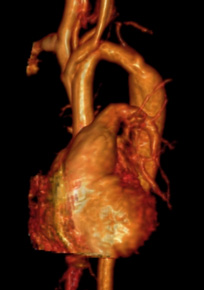

Coronary Problems

Description: The coronary arteries provide blood supply to the heart. Children can have coronary problems that are different from adults. Children can be born with the coronary arteries in the wrong location, called an anomalous coronary. Children can also have Kawasaki Disease which occurs with a prolonged fever and sometimes causes the coronary arteries to become abnormally large or form aneurysms.

Why MRI: Heart MRI is used to see if the coronary arteries are in the correct location and if there may be a risk of blocking flow. Heart MRI can also look for any abnormal enlargement. Sometimes a medication can be given through an IV to perform a stress test to see if there are problems with blood flow in the coronary arteries when the heart is working harder.

Images: Anomalous left or right coronary, Kawasaki, 3D coronaries